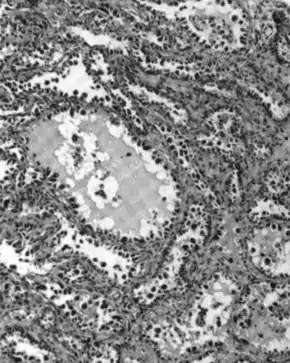

Micrograph of serous carcinoma, a type of ovarian cancer, diagnosed in peritoneal fluid

Diagnosis of ovarian cancer starts with a physical examination (including a pelvic examination), a blood test (for CA-125 and sometimes other markers), and transvaginal ultrasound.[17][39] Sometimes a rectovaginal examination is used to help plan a surgery.[20] The diagnosis must be confirmed with surgery to inspect the abdominal cavity, take biopsies (tissue samples for microscopic analysis), and look for cancer cells in the abdominal fluid. This helps to determine if an ovarian mass is benign or malignant.[17]

Most people with epithelial ovarian carcinoma, about two-thirds, have a serous carcinoma,[19] though this proportion is estimated as high as 80%.[22][48] Low-grade serous carcinoma is less aggressive than high-grade serous carcinomas, though it does not typically respond well to chemotherapy or hormonal treatments.[19] Serous carcinomas are thought to begin in the Fallopian tube.[47] Histologically, serous adenocarcinomas have psammoma bodies. Low-grade serous adenocarcinomas resemble Fallopian tube epithelium, whereas high-grade serous adenocarcinomas show anaplasia and nuclear atypia.[20]

50% of the time, serous carcinomas are bilateral, and in 85% of cases, they have spread beyond the ovary at the time of diagnosis. Most have a diameter over 15 cm.[48]